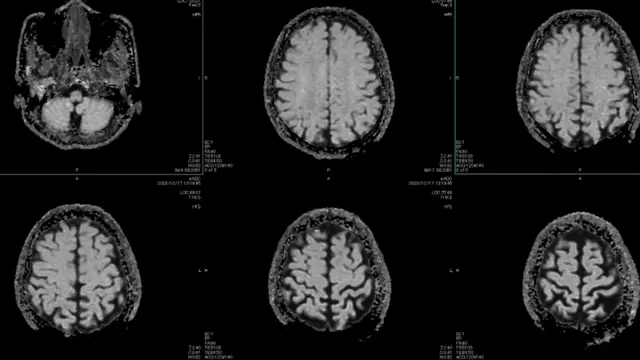

A principal teoria entre os cientistas que estudam o papel do cérebro na enxaqueca é que o ataque é uma onda elétrica lenta e anormal, que se espalha através do córtex cerebral, conhecida como depressão cortical alastrante (CSD, na sigla em inglês).

Esta onda suprime a atividade cerebral e faz disparar os nervos próximos que causam a dor, fazendo soar o alarme e gerando inflamações.

Em março de 2025, cientistas capturaram a onda em tempo real, enquanto monitoravam o cérebro de uma paciente de 32 anos, sendo preparada para cirurgia. Eles captaram a onda através de 95 eletrodos inseridos no seu crânio.

Ela se espalhou a partir do seu córtex visual, o que explica por que algumas pessoas apresentam sensibilidade à luz e visões de auras, segundo Moskowitz. Dali, ela atravessou todo o cérebro por mais 80 minutos.

A variação da natureza da onda ajuda a explicar por que algumas pessoas veem apenas uma aura, outras veem uma aura antes da dor de cabeça e há um grupo que tem dor de cabeça antes da aura, segundo Moskowitz. Tudo depende dos padrões da onda.

Mas a depressão cortical alastrante também explica outros sintomas neurológicos que surgem durante um ataque de enxaqueca, como a fadiga, bocejos, nevoeiro cerebral e vontade de comer alimentos específicos.